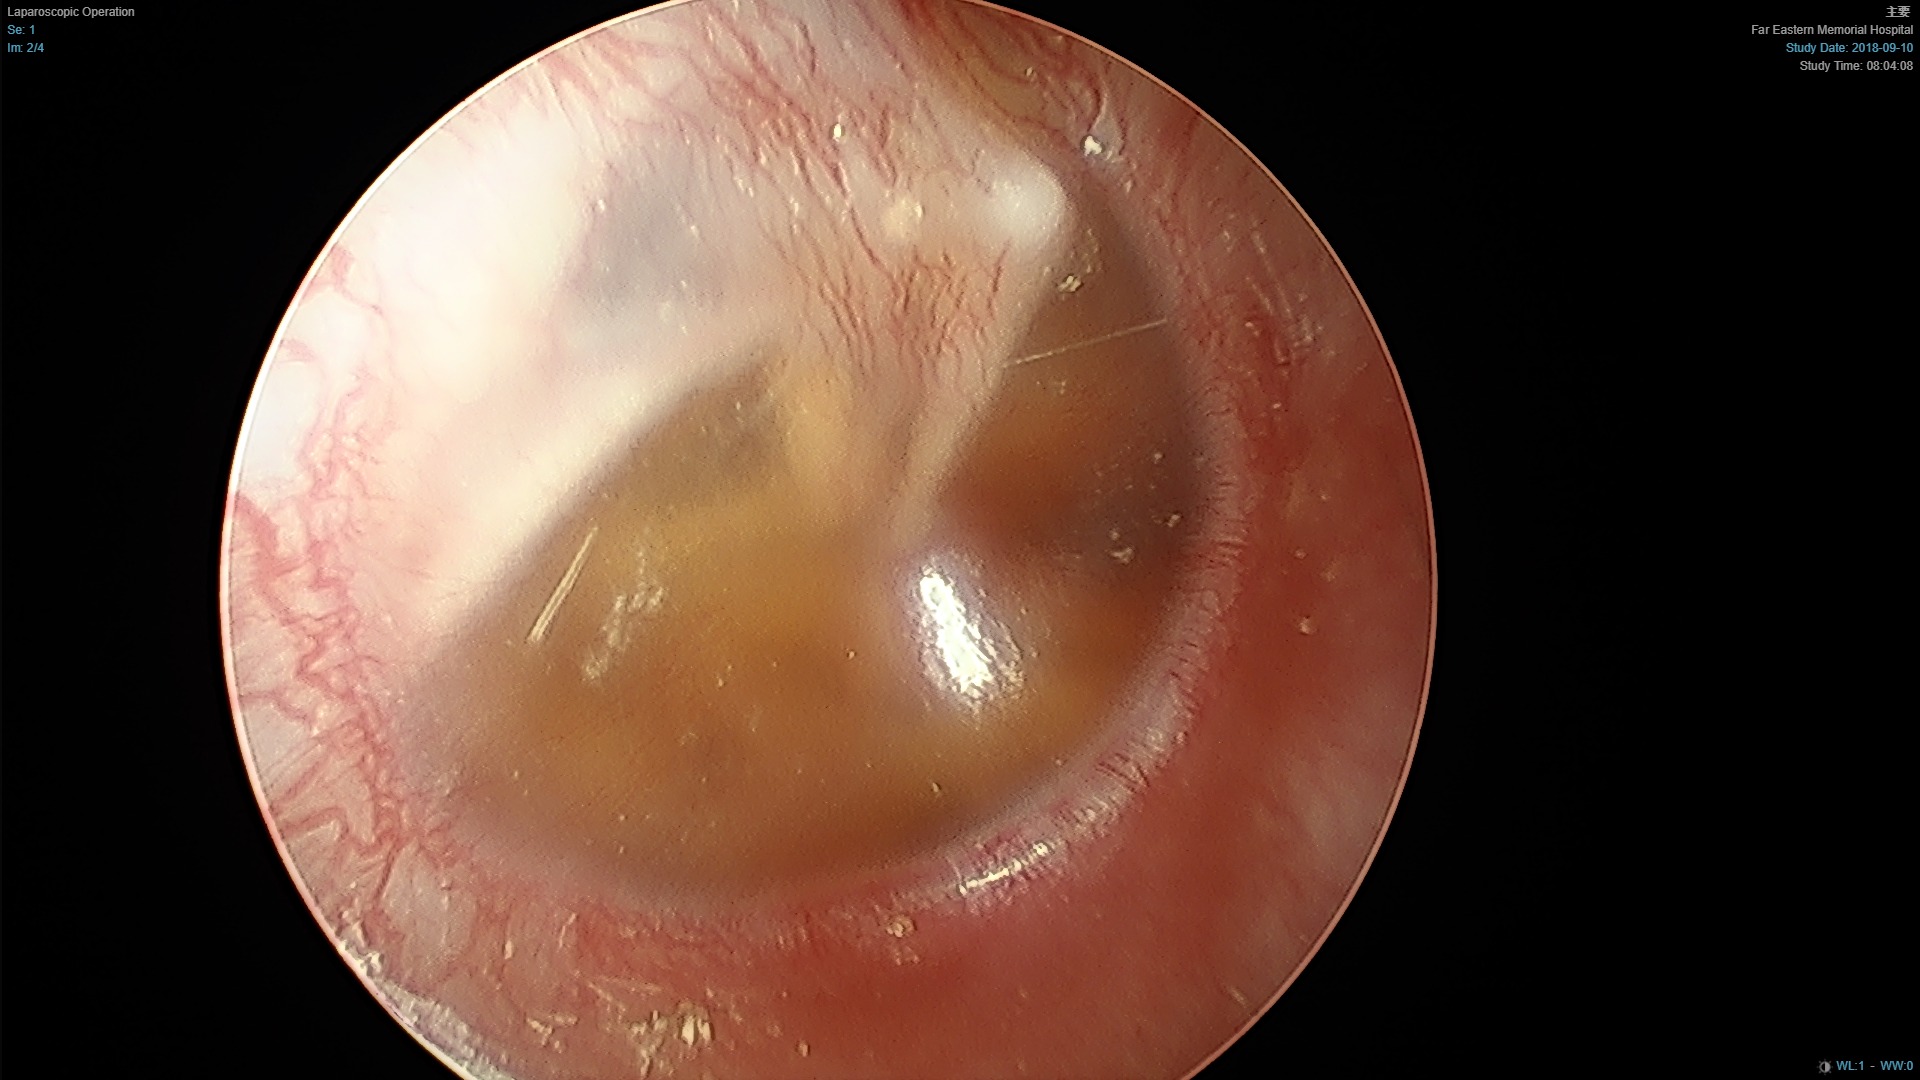

- 中耳積水

中耳積液